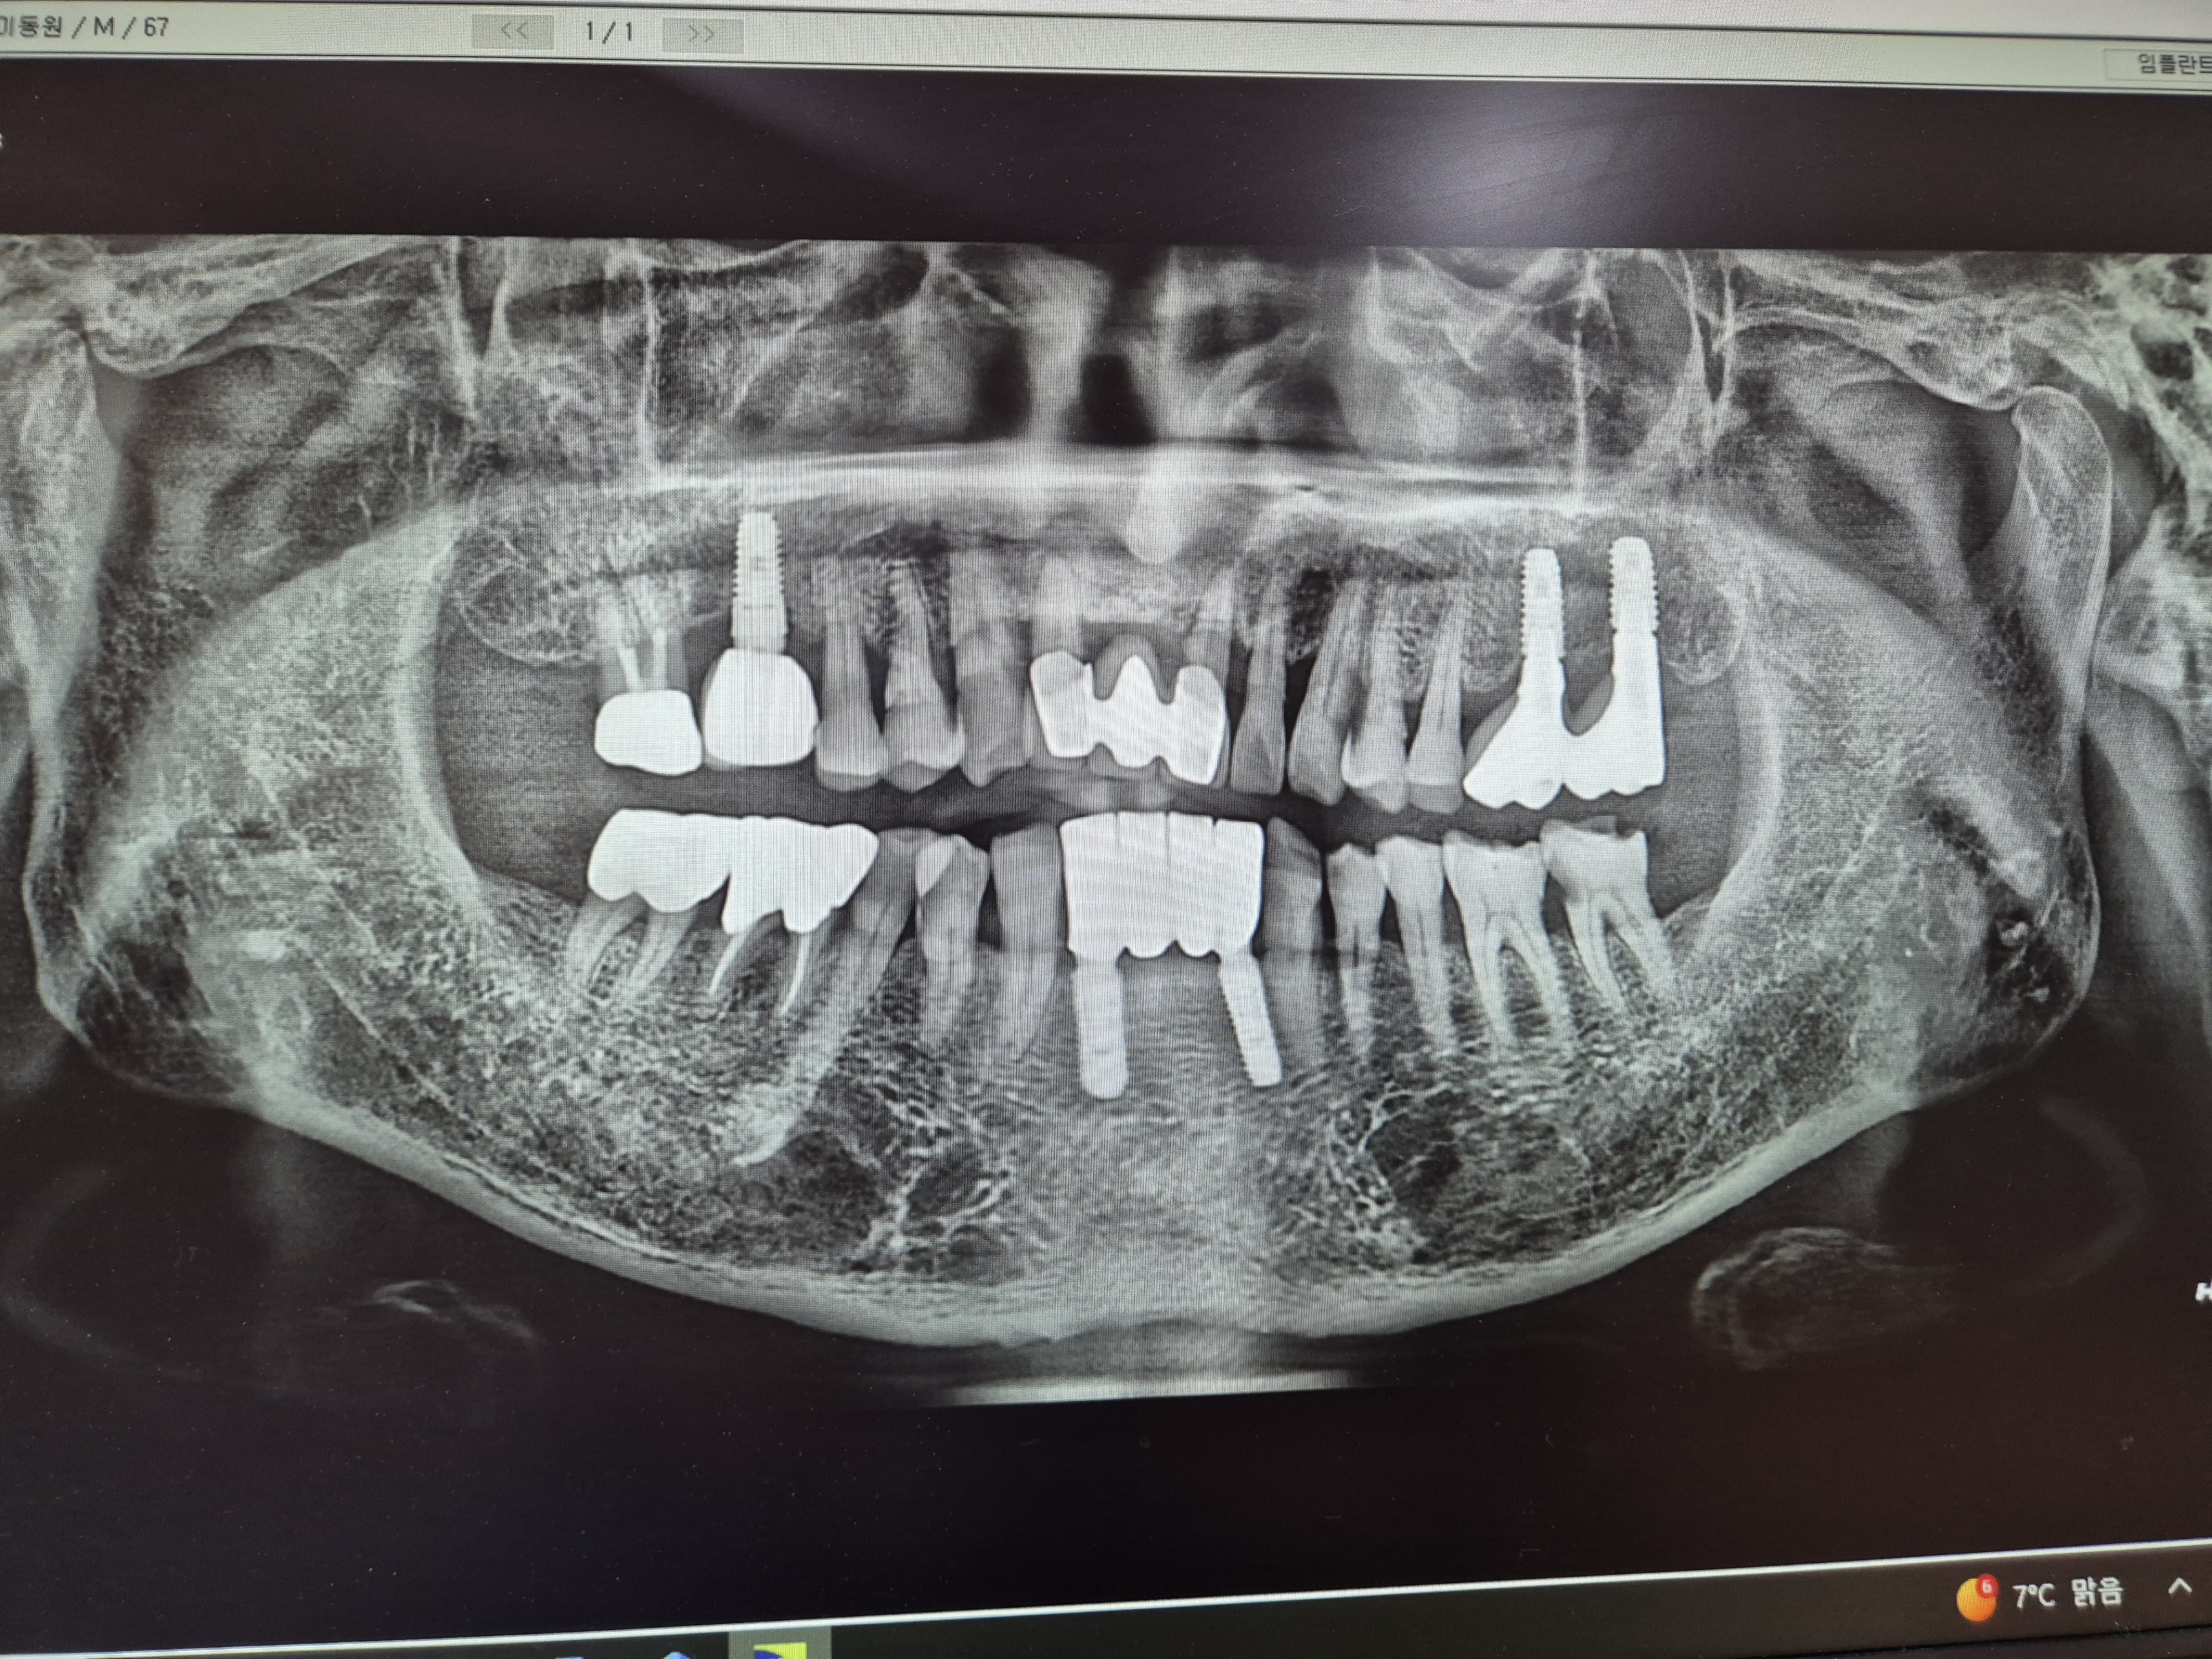

치아사진을 보니 5개의 임플란트와 덧씌우거나 치료받은 이빨이 10개정도.

총체적으로 건강하지못한 치아상태이다.